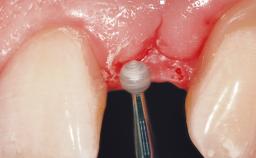

A 33-year-old female patient presented with an upper left central incisor that required extraction after a failed endodontic therapy. The tooth had been traumatized when the patient was a teenager and had undergone several endodontic treatments, including two apicectomy procedures. The patient was in good health and did not smoke. Clinical examination showed that the patient had a high lip line. In full smile, the gingival margins of the upper teeth were visible to the first molars. The gingival margins of central incisors 11 and 21 were only just showing. Examination of tooth 21 confirmed that the tooth was mobile and had hypererupted by 1 mm.

Placement Protocol Immediate implant placement

Tooth Site Maxillary incisor or canine

Socket Morphology Single-root socket

Socket Integrity Damage to one or more bone walls